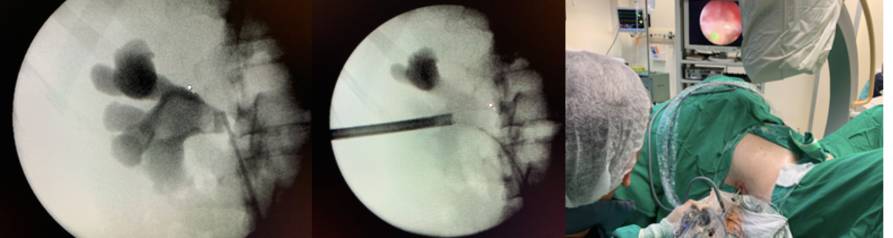

Figura 2 – criança de 11 meses submetida a mini percutânea.

Figura 3 – cálculo de 30mm em pelve submetido a tratamento com camisa de 19.5F

O sistema de Mini Percutânea Mistra é composto por um endoscópio fino de 12F, com alta resolução de 40.000 pixels em alta resolução, três camisas com diâmetro de 15/18 F., 16.5/19.5 F. e 21/24 F com seus respectivos dilatadores. O conjunto promove versatilidade para a cirurgia e já faz parte do arsenal terapêutica da endourologia.